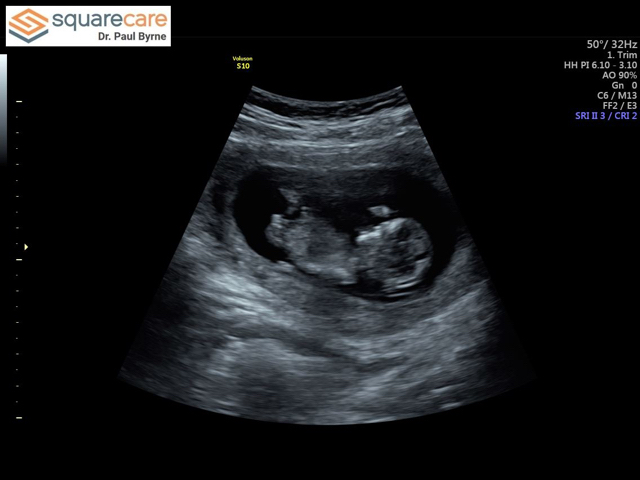

Gender guesses!!!! 12w3d!! Due June 10th!!

Y’all here is my little one at 12 weeks yesterday!! It’s so unreal!! Had all the genetics blood work done and for gender as well but I’m so torn on if I want to know or not!

This baby is a surprise and I’m unprepared. My sister wants to throw me a sprinkle because I didn’t have one with my son. Is a gender neutral sprinkle okay? Ugh torn! Any guesses from the sono pic what I might be having?? According to the Chinese gender calendar it’s a girl and it was right for both of my other children!!